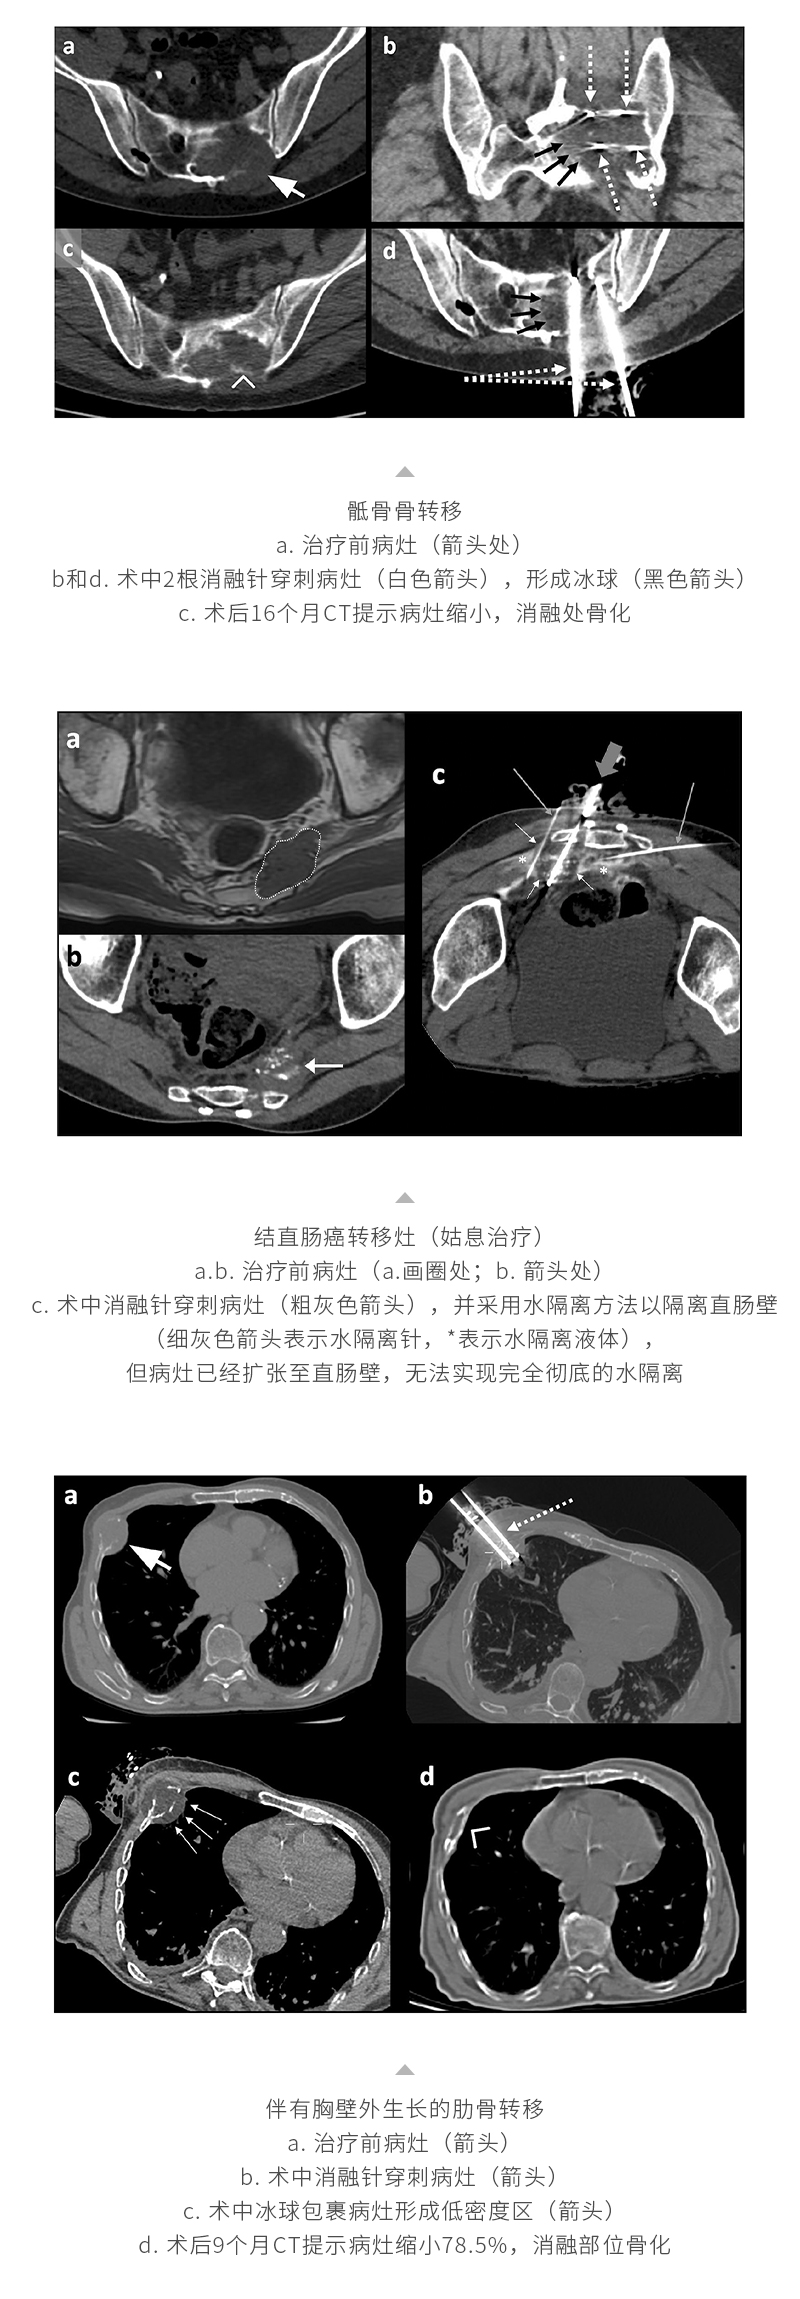

冷冻消融转移性骨肿瘤——【海杰亚科研资讯】第268期